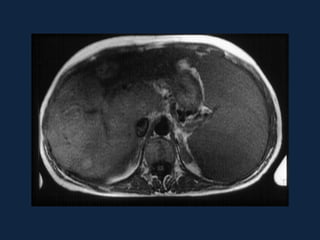

ESTEATOSE HEPÁTICA

ACENTUADA

• Ocorre uma diminuição na eficácia da TC de

identificar lesões focais hepáticas.

• Pode ocorrer uma inversão no padrão visual das

lesões focais, em relação às comparações usuais de

atenuação feitas com o fígado normal.

MULTINODULAR

• Forma mais rara de esteatose hepática.

• É fundamental a correlação com dados

clínicos e com estudos de RM para excluir

doença metastática.